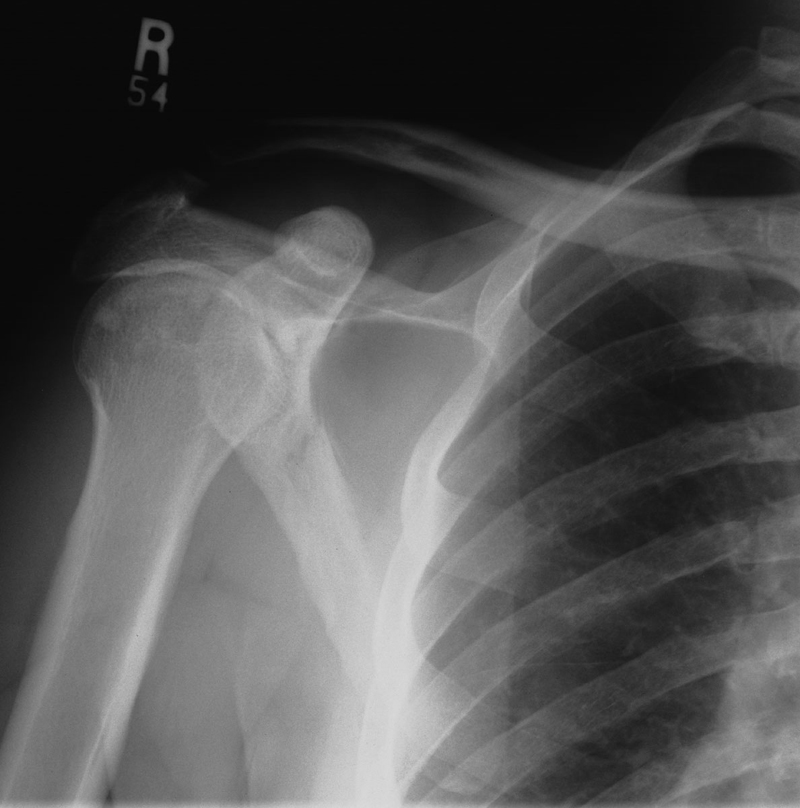

Scapular Fracture

The scapula is embedded in muscle, and is not easily fractured. This radiograph of a medical student in the class of 2008 shows what can be accomplished with enough determination.